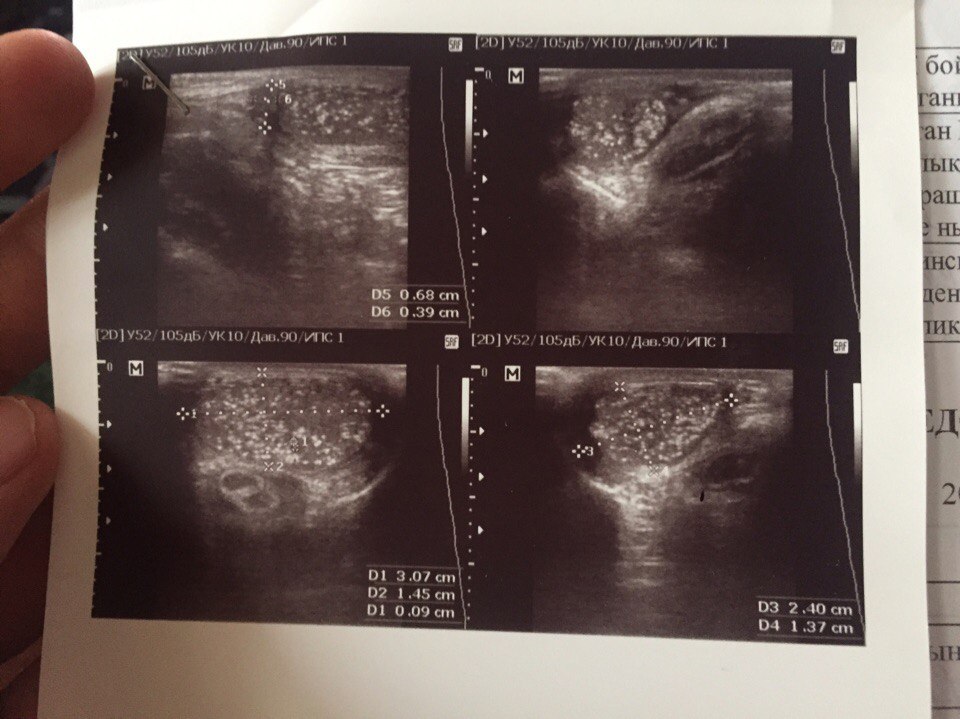

Доброго времени суток! есть вопрос, у моему сыну 10 лет 8 месяцев,сделали УЗИ яичек, Заключение: множественные кальценаты обоих яичек. Какие последствия могут быть если не лечить это? как нужно лечить? в дальнейшем на спермаграмму будет влиять и на потомство повышенные кальценаты и если можете дать по больше информации на счет этого всего. 3 года делаем УЗИ и все три года такой диагноз.

изображение 1 изображение 2 изображение 3

Ответ нашего специалиста: Множественные кальцинаты яичек являются признаком хронического орхоэпидидимита. Последствия могут быть плачевные. Как нужно лечить пока не понятно. Вам необходимо подойти на консультацию.